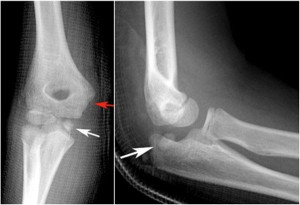

Trật khớp khuỷu tay xảy ra khi các đầu xương tạo nên khớp khuỷu tay bị lệch khỏi vị trí bình thường. Điều này thường là do chống tay xuống đất khi ngã. Khớp khuỷu tay là vị trí khớp bị trật phổ biến thứ hai ở người lớn (chỉ sau khớp vai) và là vị trí khớp bị trật phổ biến nhất ở trẻ em.